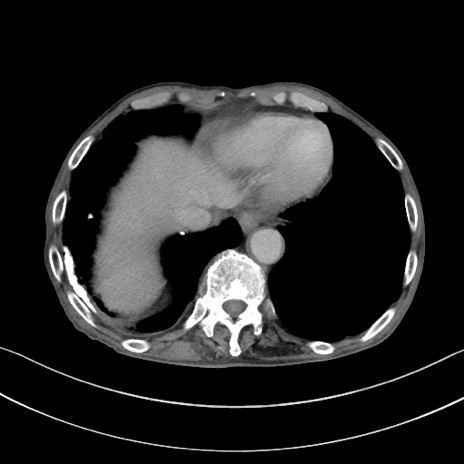

【症例】 70歳代男性

【主訴】右鼠径部腫瘤、疼痛

【現病歴】本日朝より上記主訴あり、受診。

【既往歴】膀胱癌にて膀胱全摘、両側尿管皮膚瘻

【データ】WBC 5600、CRP 0.56